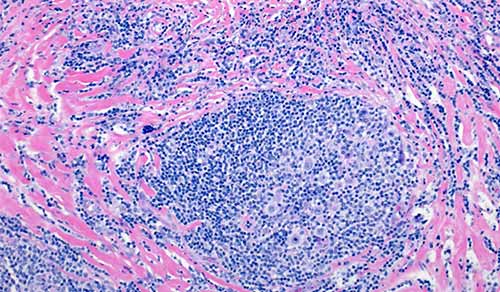

Fighting cancer takes a team, and our pediatric oncology team at the Children's Hospital of New York is made up of internationally recognized specialists who collaborate to provide individualized care for each patient. We provide access to groundbreaking pediatric clinical trials and are the only institution in New York designated by the National Cancer Institute to conduct Phase I pediatric clinical trials — the earliest phase of studies for patients.

Pediatric Oncology (Cancer)